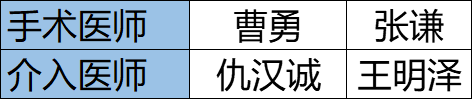

今天为大家分享的是来自首都医科大学附属北京天坛医院神经外科曹勇主任医师、张谦副主任医师担任手术医师,仇汉诚副主任医师、王明泽医生担任介入术者的靶向栓塞供血动脉辅助的脑动静脉畸形切除术,欢迎阅读分享!